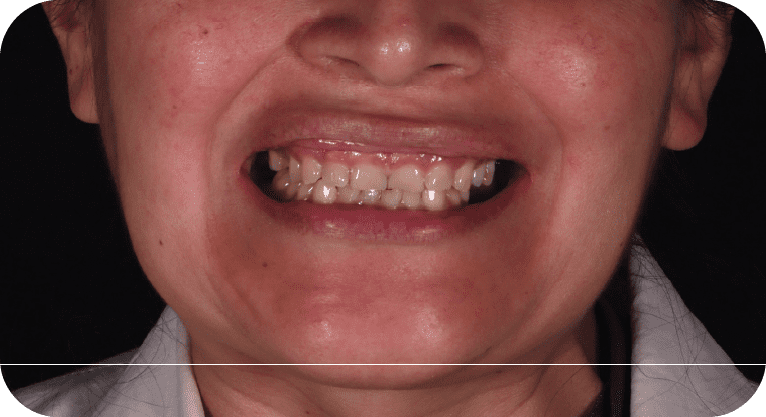

Paciente femenino, “29” años

Tratamiento: Carillas dentales

El paciente acudió a la clínica dental por inconformidad con la forma y posición de sus dientes. Tras una evaluación personalizada, se realizó un diseño de sonrisa con carillas dentales para mejorar su estética dental, logrando resultados naturales y satisfactorios.